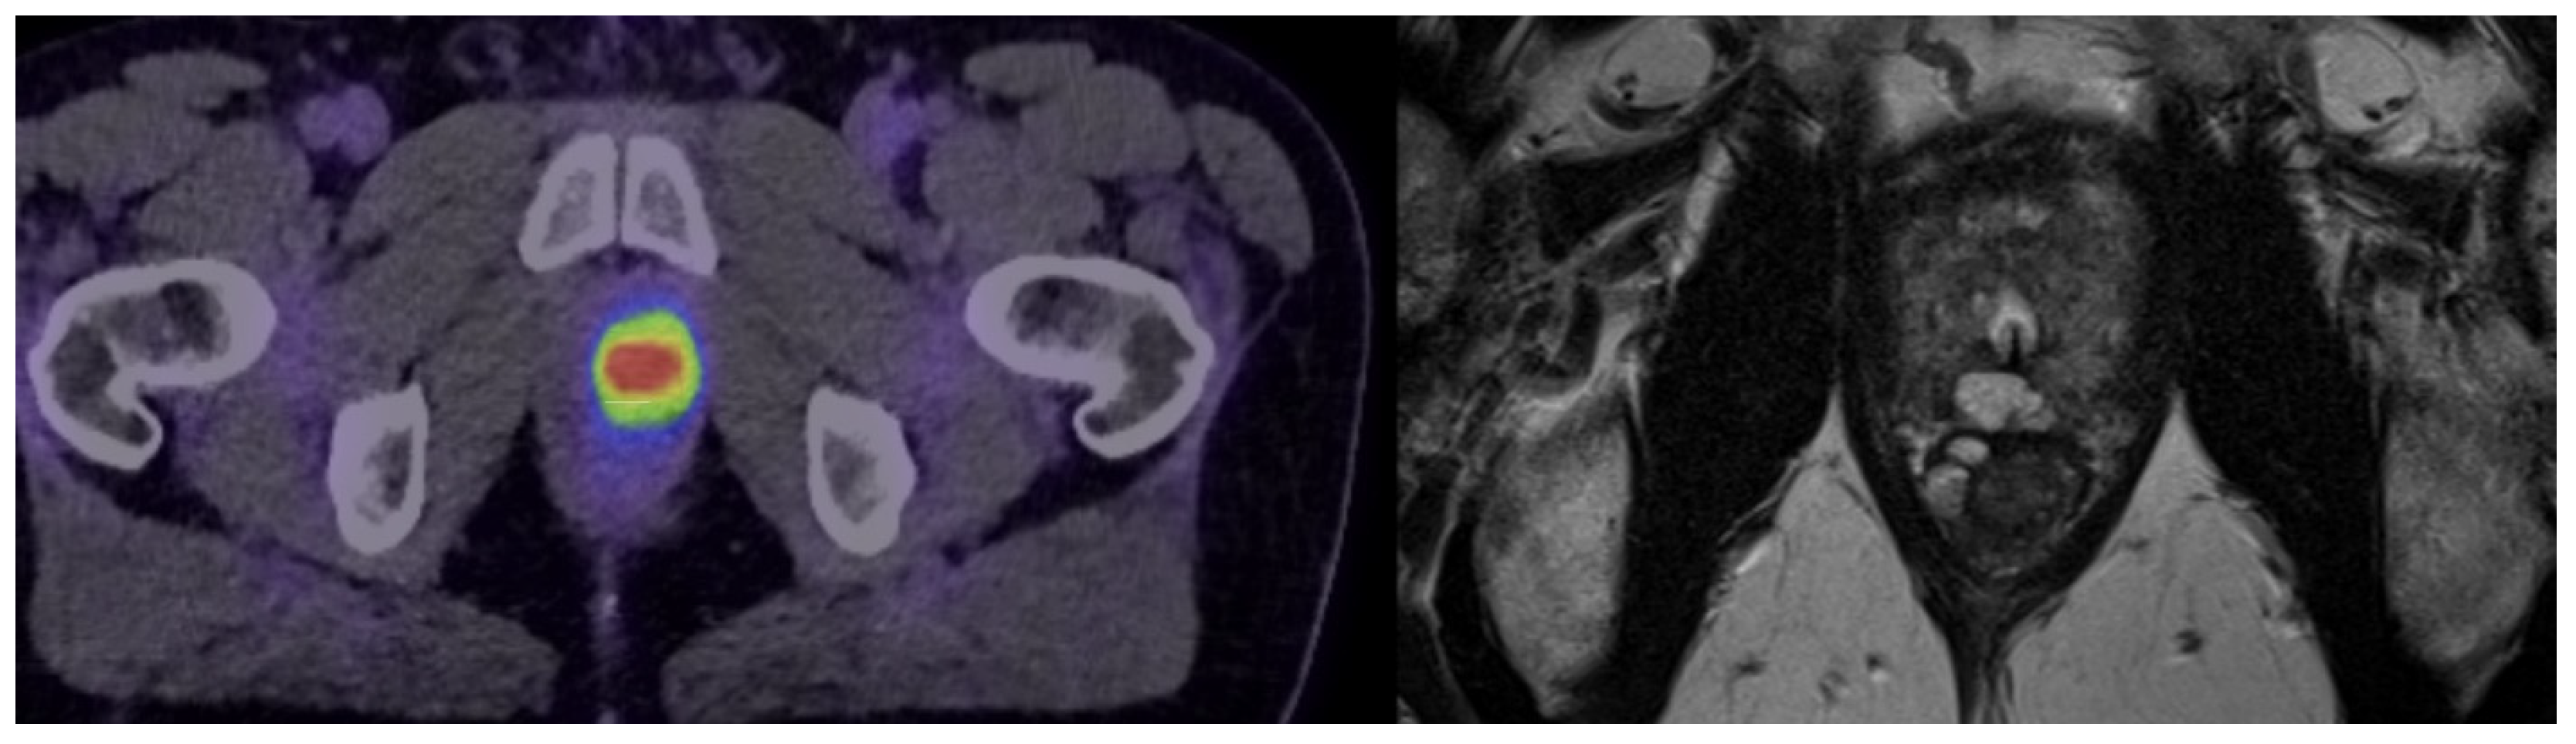

In low- to intermediate-risk PCa, PSMA PET scans identified MRI occult lesions in 12.3–29% of patients, of which up to 10% may harbour underlying unfavourable pathology that may not be suitable for active surveillance [17]. MRI-occult lesions (Figure 2) are defined as areas of concern that are not visible or detectable on MRI but are identified on alternative imaging modalities such as PSMA PET scans. PSMA PET scans can potentially improve patient selection during active surveillance by identifying aggressive disease, which may be better managed with active treatment. This improves risk stratification and prevents patient misclassification. However, these findings are limited by the fact that most existing studies are retrospective in nature with small sample sizes. Therefore, further prospective trials are needed.

Figure 2.

Example of an MRI-occult lesion (transverse imaging), which was not visible on mpMRI and classified as PI-RADS 2 (image on the right). However, the lesion was detected as a PSMA-avid lesion on 18F PSMA PET/CT (image on the left). MRI-occult lesions are those that do not show up clearly on MRI scans but are detected using alternative imaging techniques, such as PSMA PET. Abbreviations: Prostate Imaging–Reporting and Data System (PIRADS), prostate-specific membrane antigen positron emission tomography (PSMA PET), multiparametric magnetic resonance imaging (mpMRI).